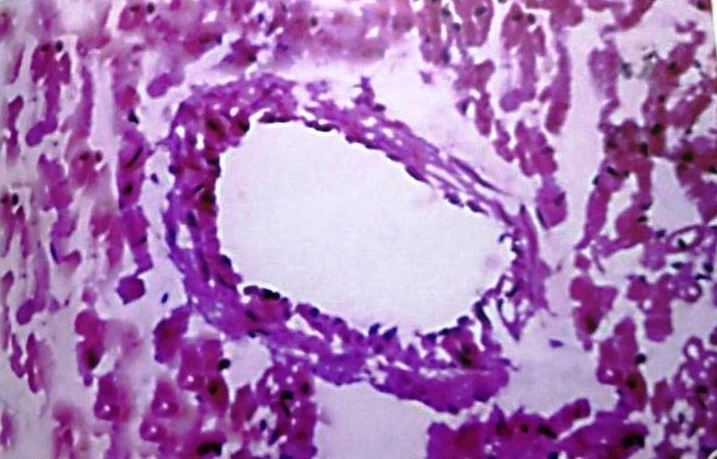

Coronary artery

The coronary artery of control group animals showed the lumen encircled by the arterial wall, which consisted of three distinct layers tunica intima, tunica media and tunica adventitia. The coronary arteries of hyper-cholesterolemic rabbits (Group II) showed foamy appearance, due to the presence of a large number of lipid-filled macrophages. The wall becomes very thick, reducing the size of the lumen. Our findings demonstrated that concurrent administration of C. verum extract with high cholesterol diet caused a significant increase in lumen size and thickening of tunica intima due to foam cell showed a reduction. However, the plaque has restricted to grow in concurrent groups, but coronary artery of low dose level treated group showed some fatty changes. (fig. 7-10)

Fig. 7: Coronary artery of control rabbit

Fig. 8: Coronary artery of rabbit after Athero Diet feeding for 120 d

Fig. 9: Coronary artery of rabbit–Athero Diet+C. verum 200 mg concurrent (120 d)

Fig. 10: Coronary artery of rabbit-Athero Diet+C. verum 300 mg concurrent (120 d)